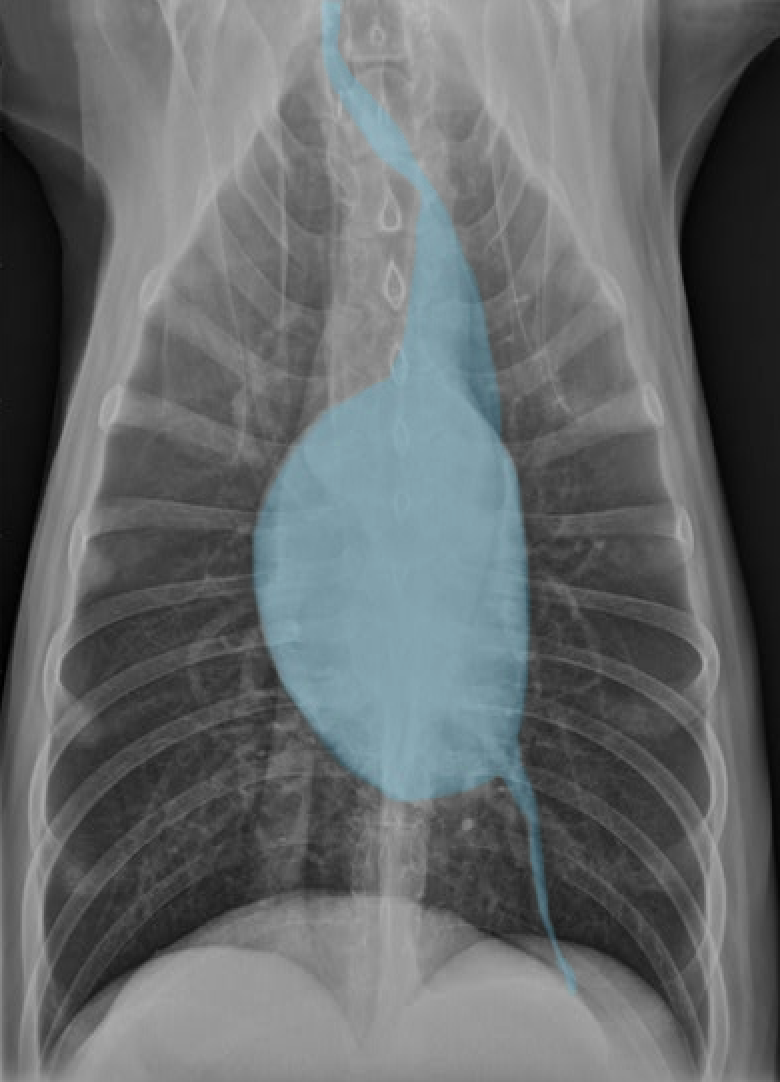

identify the structures

RA: right auricle (atrium)

RV: right ventricle

LV: left ventricle

LA: left atrium

A: aorta

C: caudal vena cava

T: trachea